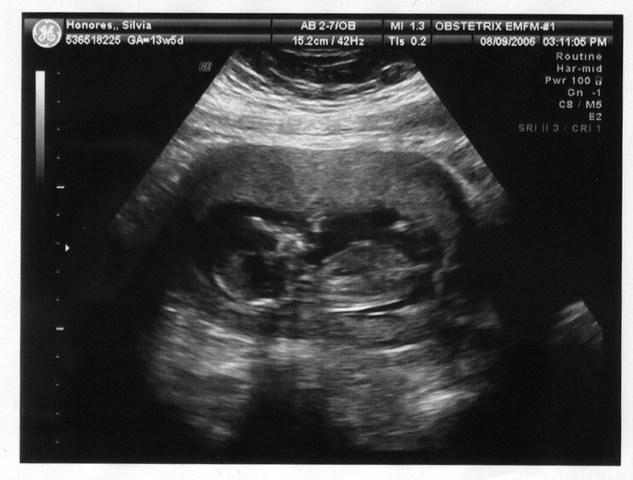

• SEMANA 13

SEMANA 13

La 13ª semana del embarazo es la última semana que se aborda dentro del primer trimestre del embarazo, un periodo que los obstetras catalogan como el más crítico de la gestación.